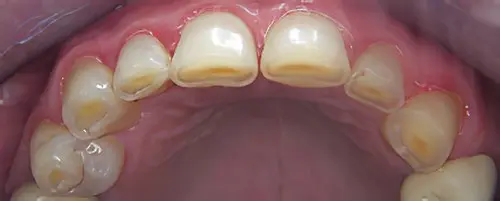

- DENTS et PROTHESES (couronnes, appareils…) : usures, fêlures, fractures, mobilités, sensibilités….